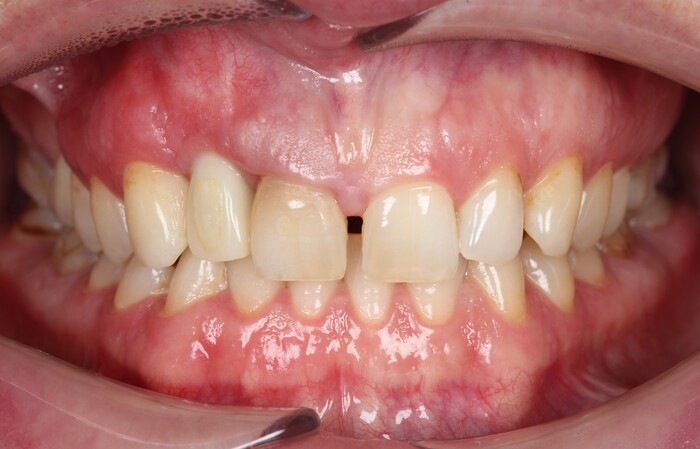

Далее проведена пластика десны, снова два месяца ожиданий и установка временной коронки:

Ну, такое, согласен, но это начало.

Еще через пару месяцев временную коронку сняли для изготовления новой:

И вот картинка спустя полгода «ношения» новой временной коронки: